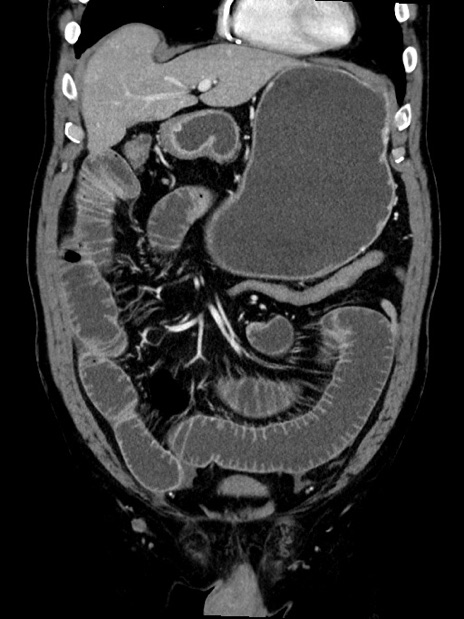

症例35(冠状断像)

【症例】70歳代 男性

【主訴】腹部膨満、嘔吐

【現病歴】昨日より腹部膨満感出現。本日増悪し、仙痛出現。嘔吐あり、受診。

【既往歴】糖尿病、胆摘後

【身体所見】BP 149/80mmHg、HR 74/min、BT 35.9℃、腹部:膨満、軟、圧痛なし。腸雑音減弱あり。上腹部正中切開瘢痕あり。

【データ】WBC 13500、CRP 1.72